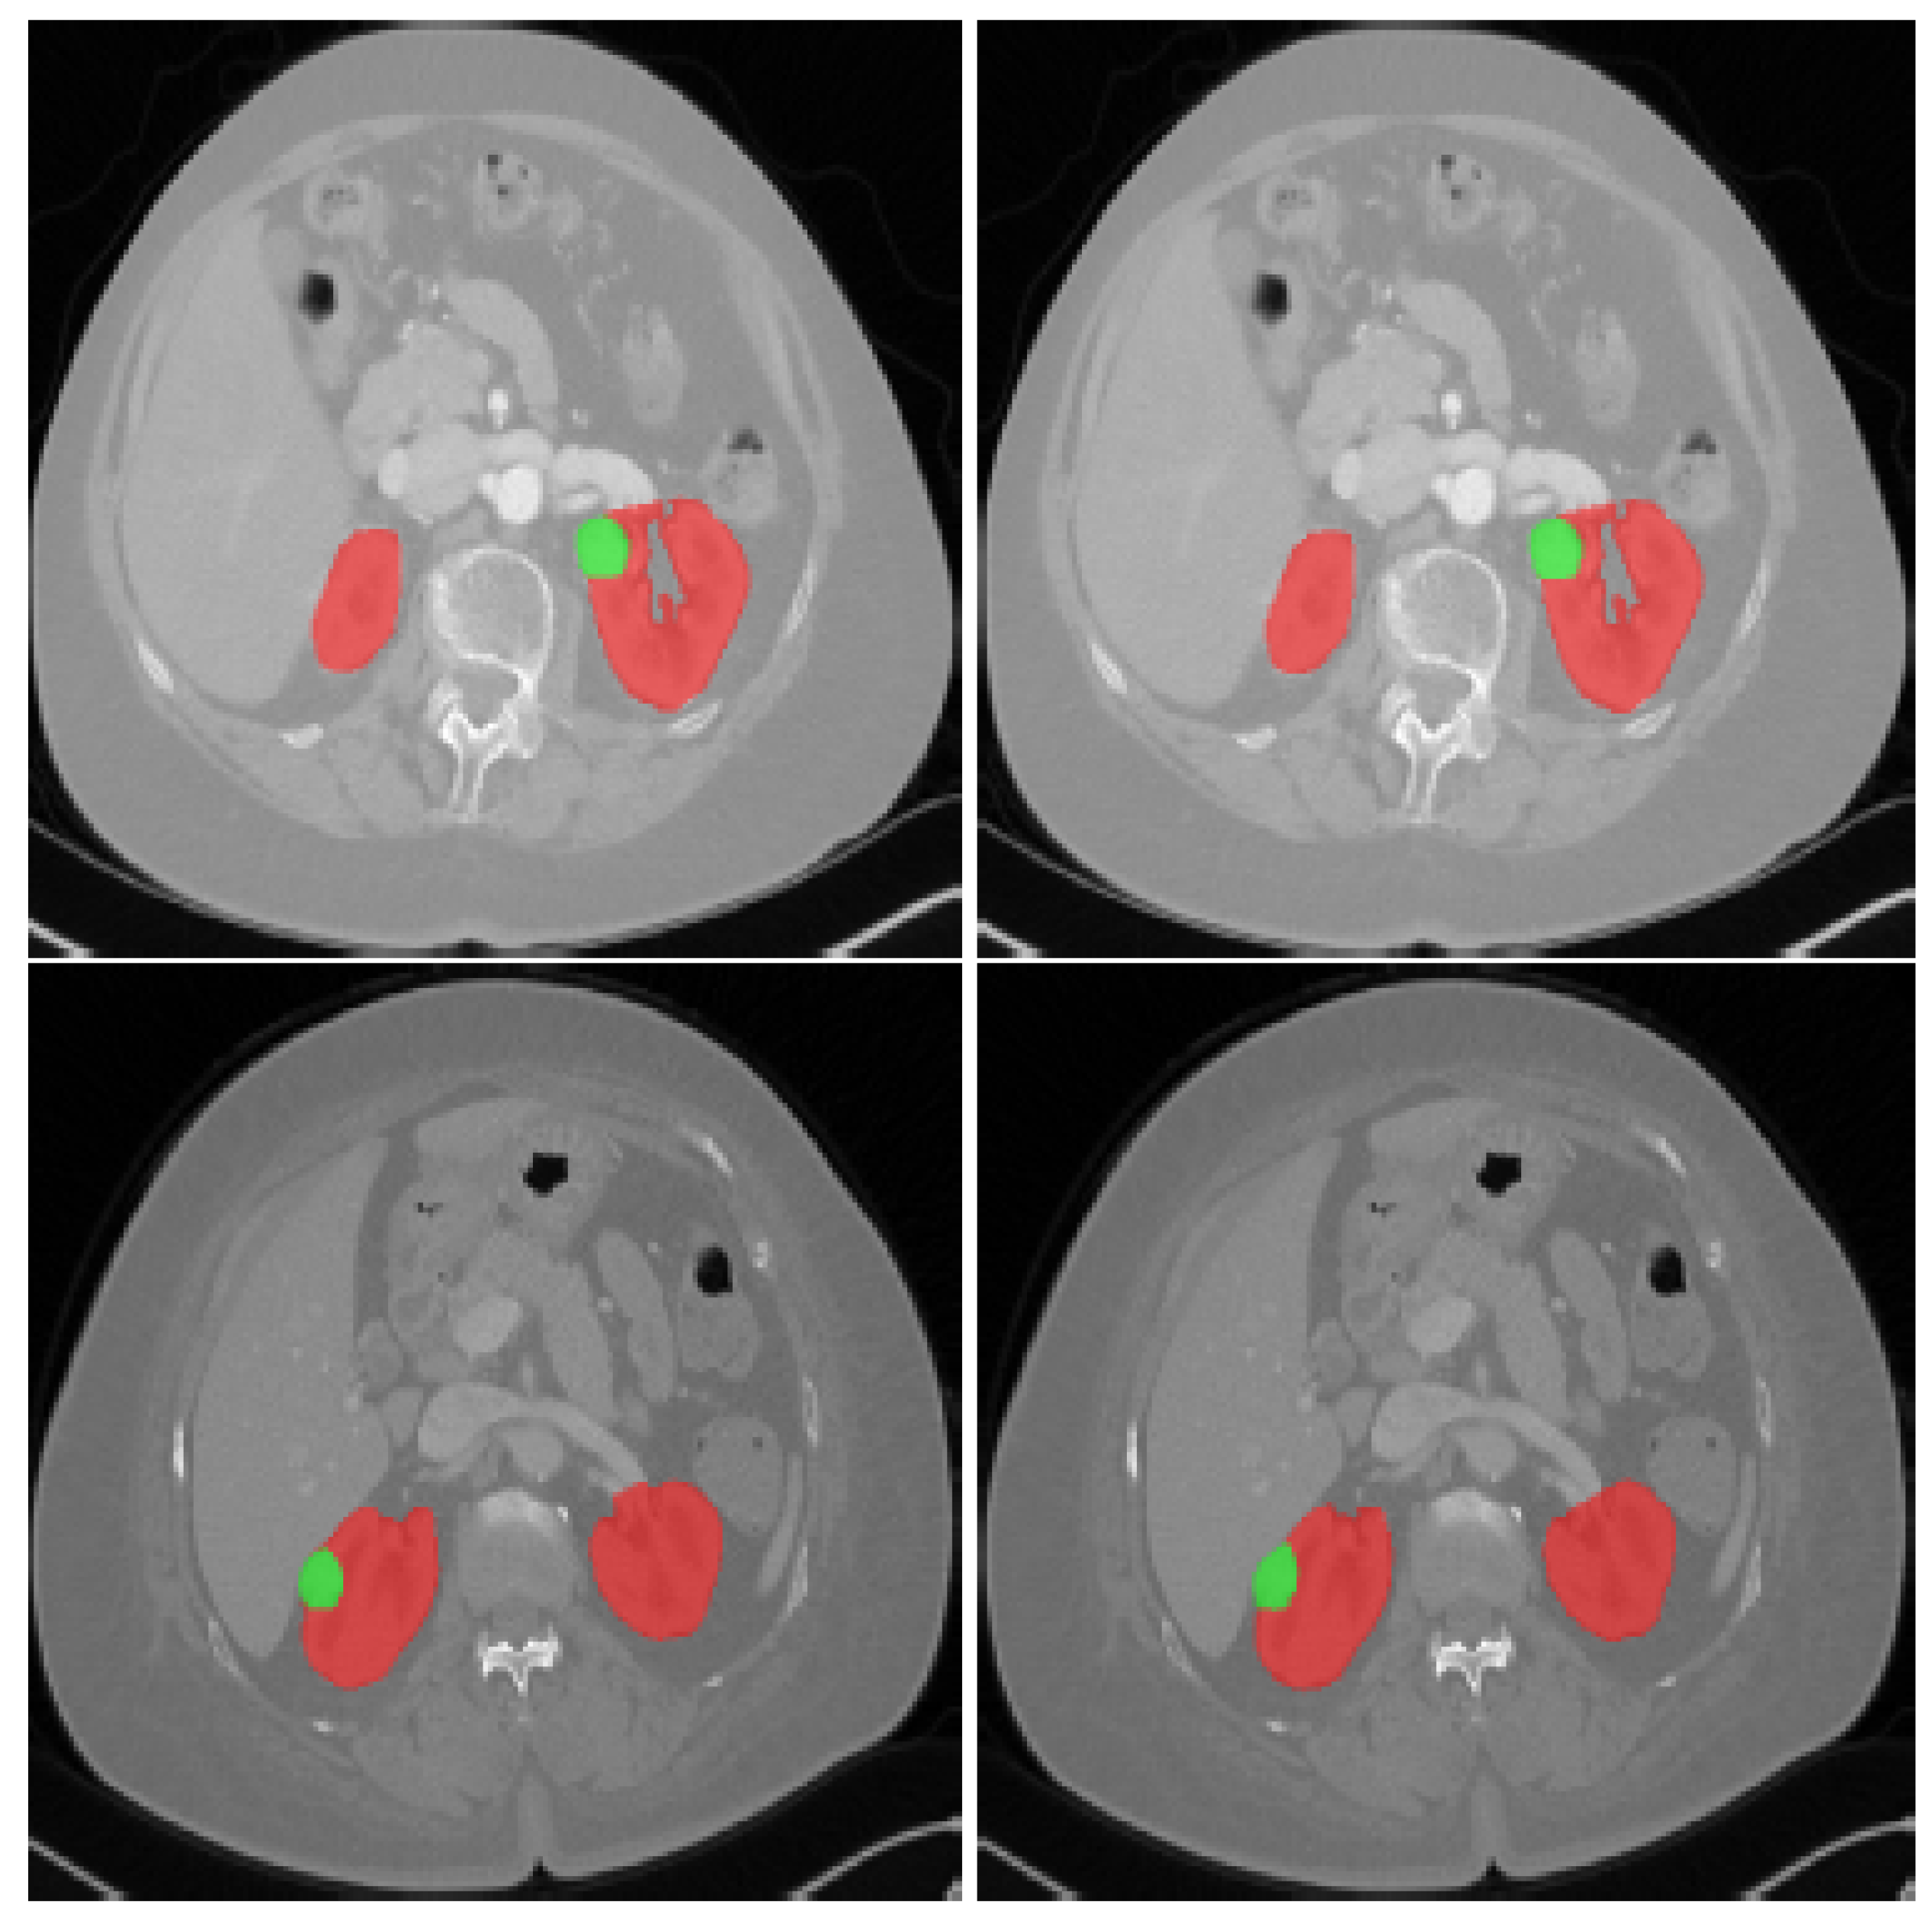

Figure 2.

CT scans showing: An axial slice of two patients’ 3D CT scans from the KiTS19 dataset; the red tint denotes the kidneys, whereas the green color indicates the tumor site [5].